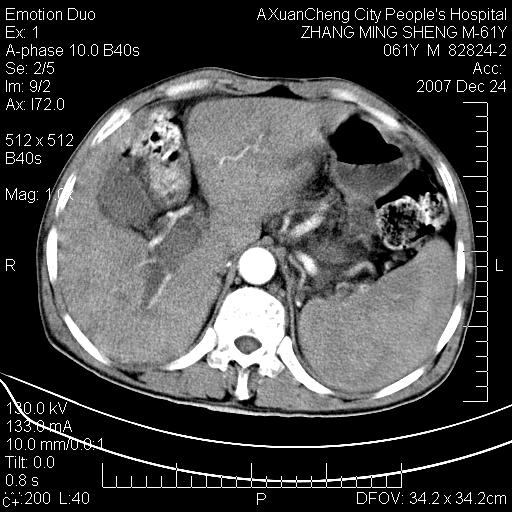

标题: CT11031:M61Y,胰腺占位

大家侃侃门静脉和胆管系统怎么回事,肝内转移?

胰腺癌肝转移

2,肝内多发结节状低密度占位,伴门脉及肠系膜上v栓子形成.考虑a;门脉及肠系膜上v血栓后肝改变.b;弥漫型肝癌伴门脉及肠系膜癌栓.

肝硬化,门脉高压,脾肿大;弥漫性肝癌,肝内、门脉、腹膜后淋巴结转移,肝内外胆管扩张,胰头区占位,建议mr检查

胰腺癌伴肝内转移;门脉、肠系膜上v癌栓形成。

考虑为:胰腺癌伴肝脏转移、腹膜后淋巴结转移,门静脉及肠系膜上静脉瘤栓形成。

胰体尾癌伴肝内转移,门静脉及肠系膜上静脉瘤栓形成.